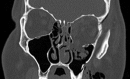

Orbital fractures are very common after facial trauma. The assessment of a patient with a suspected orbital wall injury includes a detailed oculofacial examination as well as radiologic imaging. Surgical repair with or without an implant may be indicated for diplopia, enophthalmos, or both. Cicatricial eyelid malposition is an iatrogenic complication commonly due to poor orbitotomy technique. Optimal repair involves direct exposure of the perimeter of the fractures' site through surgical planes that minimally scar the eyelids. A wide variety of implant options exist; however, thin, pliable, nonadherent materials such as nylon foil may offer several advantages. The authors describe the evaluation and management of orbital wall fractures.